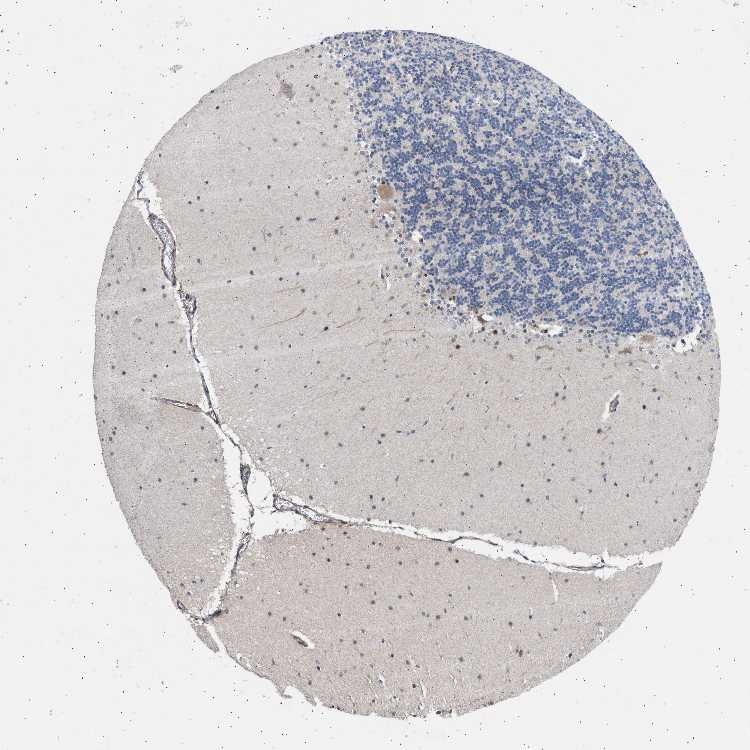

CEREBELLUM - Antibody stainingi

Antibody staining in the annotated cell types in the current human tissue is reported as not detected, low, medium, or high, based on conventional immunohistochemistry profiling in selected tissues. This score is based on the combination of the staining intensity and fraction of stained cells.

Each image is clickable and will lead to virtual microscopy that enables deeper exploration of all samples and also displays staining intensity scores, fraction scores and subcellular localization as well as patient and tissue information for each sample.

Antibody HPA014570

Purkinje cells Medium

Cells in granular layer Not detected

Cells in molecular layer Low